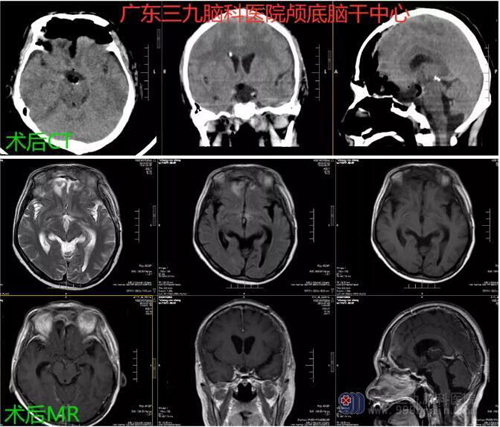

自发病起,张先生视力进行性下降,现视力仅有光感。今为求手术治疗,来广东三九脑科医院。入院后完善相关检查,2019年5月13日全麻下为患者行“鞍上、三脑室巨大颅咽管瘤切除术”,术程顺利,术后恢复良好。遗憾的是肿瘤已侵犯视神经,术后视力未恢复。病理报告示: (鞍区)乳头型颅咽管瘤WHOⅠ级

图3:术后CT及MR示鞍上、三脑室占位性病变切除术后改变